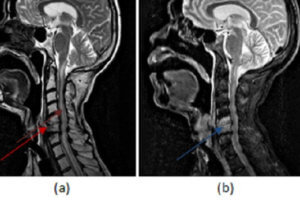

Discitis/Osteomyelitis with Epidural Phlegmon

Epidural abscess is a rare condition affecting about 2 in 10,000 patients. Spinal infection typically starts in the disc (discitis), which is seeded through hematogenous dissemination of infection, typically staph aureus and... Read more »